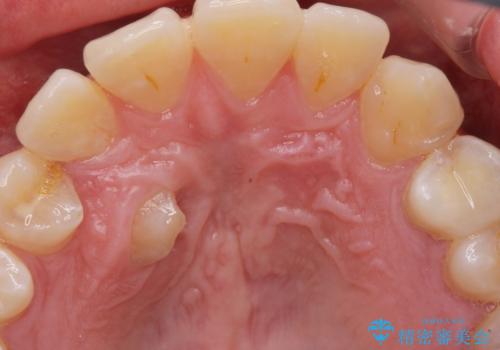

上顎の内側に歯が生えていて気になる。(静脈内鎮静下での抜歯)